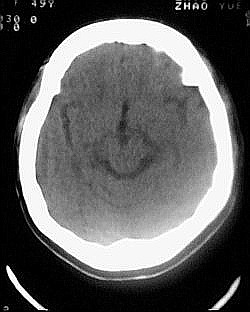

患者/49y/ 女/4年前有脑梗, 现因右侧肢体无力来院做ct扫描 ! 老师们看看这骨头有事吗?钙化点是什么原因呀??

2.双侧基底节区域多发性梗塞灶。

1、多发腔隙性脑梗塞是肯定的了。

1.双侧基底节区腔梗。

2.颅骨内外板广泛性增厚,板障狭窄甚至消失,双侧对称。无明显相应临床症状。考虑“泛发性骨皮质增厚症”。可进一步检查下颌骨及管状骨骨干。(下颌骨骨小梁增多、密集,密度增高亦为本病特点,管状骨骨干皮质向内增厚引起骨皮质厚度增加,骨密度增浓、髓腔狭窄但不消失,骨干周径较少增加)。与石骨症鉴别,后者很少影响颅盖骨和下颌骨,管状骨改变主要累及干骺端和骨骺,而骨干皮质较少增厚,椎体和髂骨翼有特征性表现。

“泛发性骨皮质增厚症,又称骨内膜增生症(endosteal hyperostosis):分为常染色体隐性遗传性疾病(van buchem)和常染色体显性遗传性骨硬化症(worth病)。后者更少见,亦较轻。两者的病理上均为骨内膜 成熟的板状新生骨形成,髓腔变窄。颅骨、颅底骨 、下颌骨,肋骨、四肢骨及骨盆骨、脊柱均可见骨内膜增生,髓腔变窄或消失,但骨外径不加大,骨骺不累及。”

本例的确应该这个病。建议楼主检查病人其他部位有无类似表现,以便确诊。